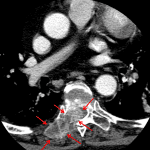

- Enhancing soft tissue mass centered in the right paraspinal musculature at T6-T7 with destruction of the adjacent superior articulating facet, lamina, transverse process, and posterior right T7 vertebral body. Additional erosion of the posterior right seventh rib as well as of the inferior right T6 and T7 articulating facets

- Enhancing soft tissue extends into the right epidural space at T6-T7 with severe associated mass effect on the thecal sac and cord

- Spinal metastasis with epidural extension

Enhancing soft tissue mass centered in the right paraspinal musculature at T6-T7 with destruction of the adjacent articulating facets, lamina, transverse process, posterior right T7 vertebral body, and posterior right seventh rib. Enhancing soft tissue extends into the right epidural space at T6-T7 with severe associated mass effect on the thecal sac and cord. Findings are most compatible with a metastatic lesion with epidural extension resulting in severe central stenosis. No evidence of pathologic fracture. T spine MRI with and without contrast can further assess extent of disease.

Additional metastatic lesion in the left eleventh rib.